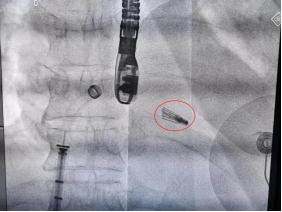

二尖瓣夹合器(红圈处)成功精准植入

明确病因后,如何治疗成为了一大难题。于波带领团队对患者整体情况进行了详细评估。由于孙先生病情危重,状态极差,此时急诊外科手术风险极高,故决定进行微创经导管二尖瓣钳夹术。术中,在全麻状态下,全程需要食道超声引导,十分考验手术医生和超声医生间的默契配合,需要操作路径、定位、角度都十分精准,就像“抓娃娃机”,稍许偏差一点就会失败。介入团队在于波指导下,陈涛、张东会和杨光经股静脉进入,默契配合,穿刺房间隔,进入左心房,准确找到二尖瓣病变位置,顺利用“夹子”夹住腱索断裂的位置,整个操作过程都是在“跳动的心脏”上完成。术后超声评估,反流由极重度变为轻微,达到了理想的效果。术后孙先生欣喜地说道:“太感谢医生了,救了我一命!术后一点都没难受,现在整个身体都感觉挺好的。抽了四十年的烟,这次我下定决心戒烟了,酒也不喝了,一定好好爱护身体!”